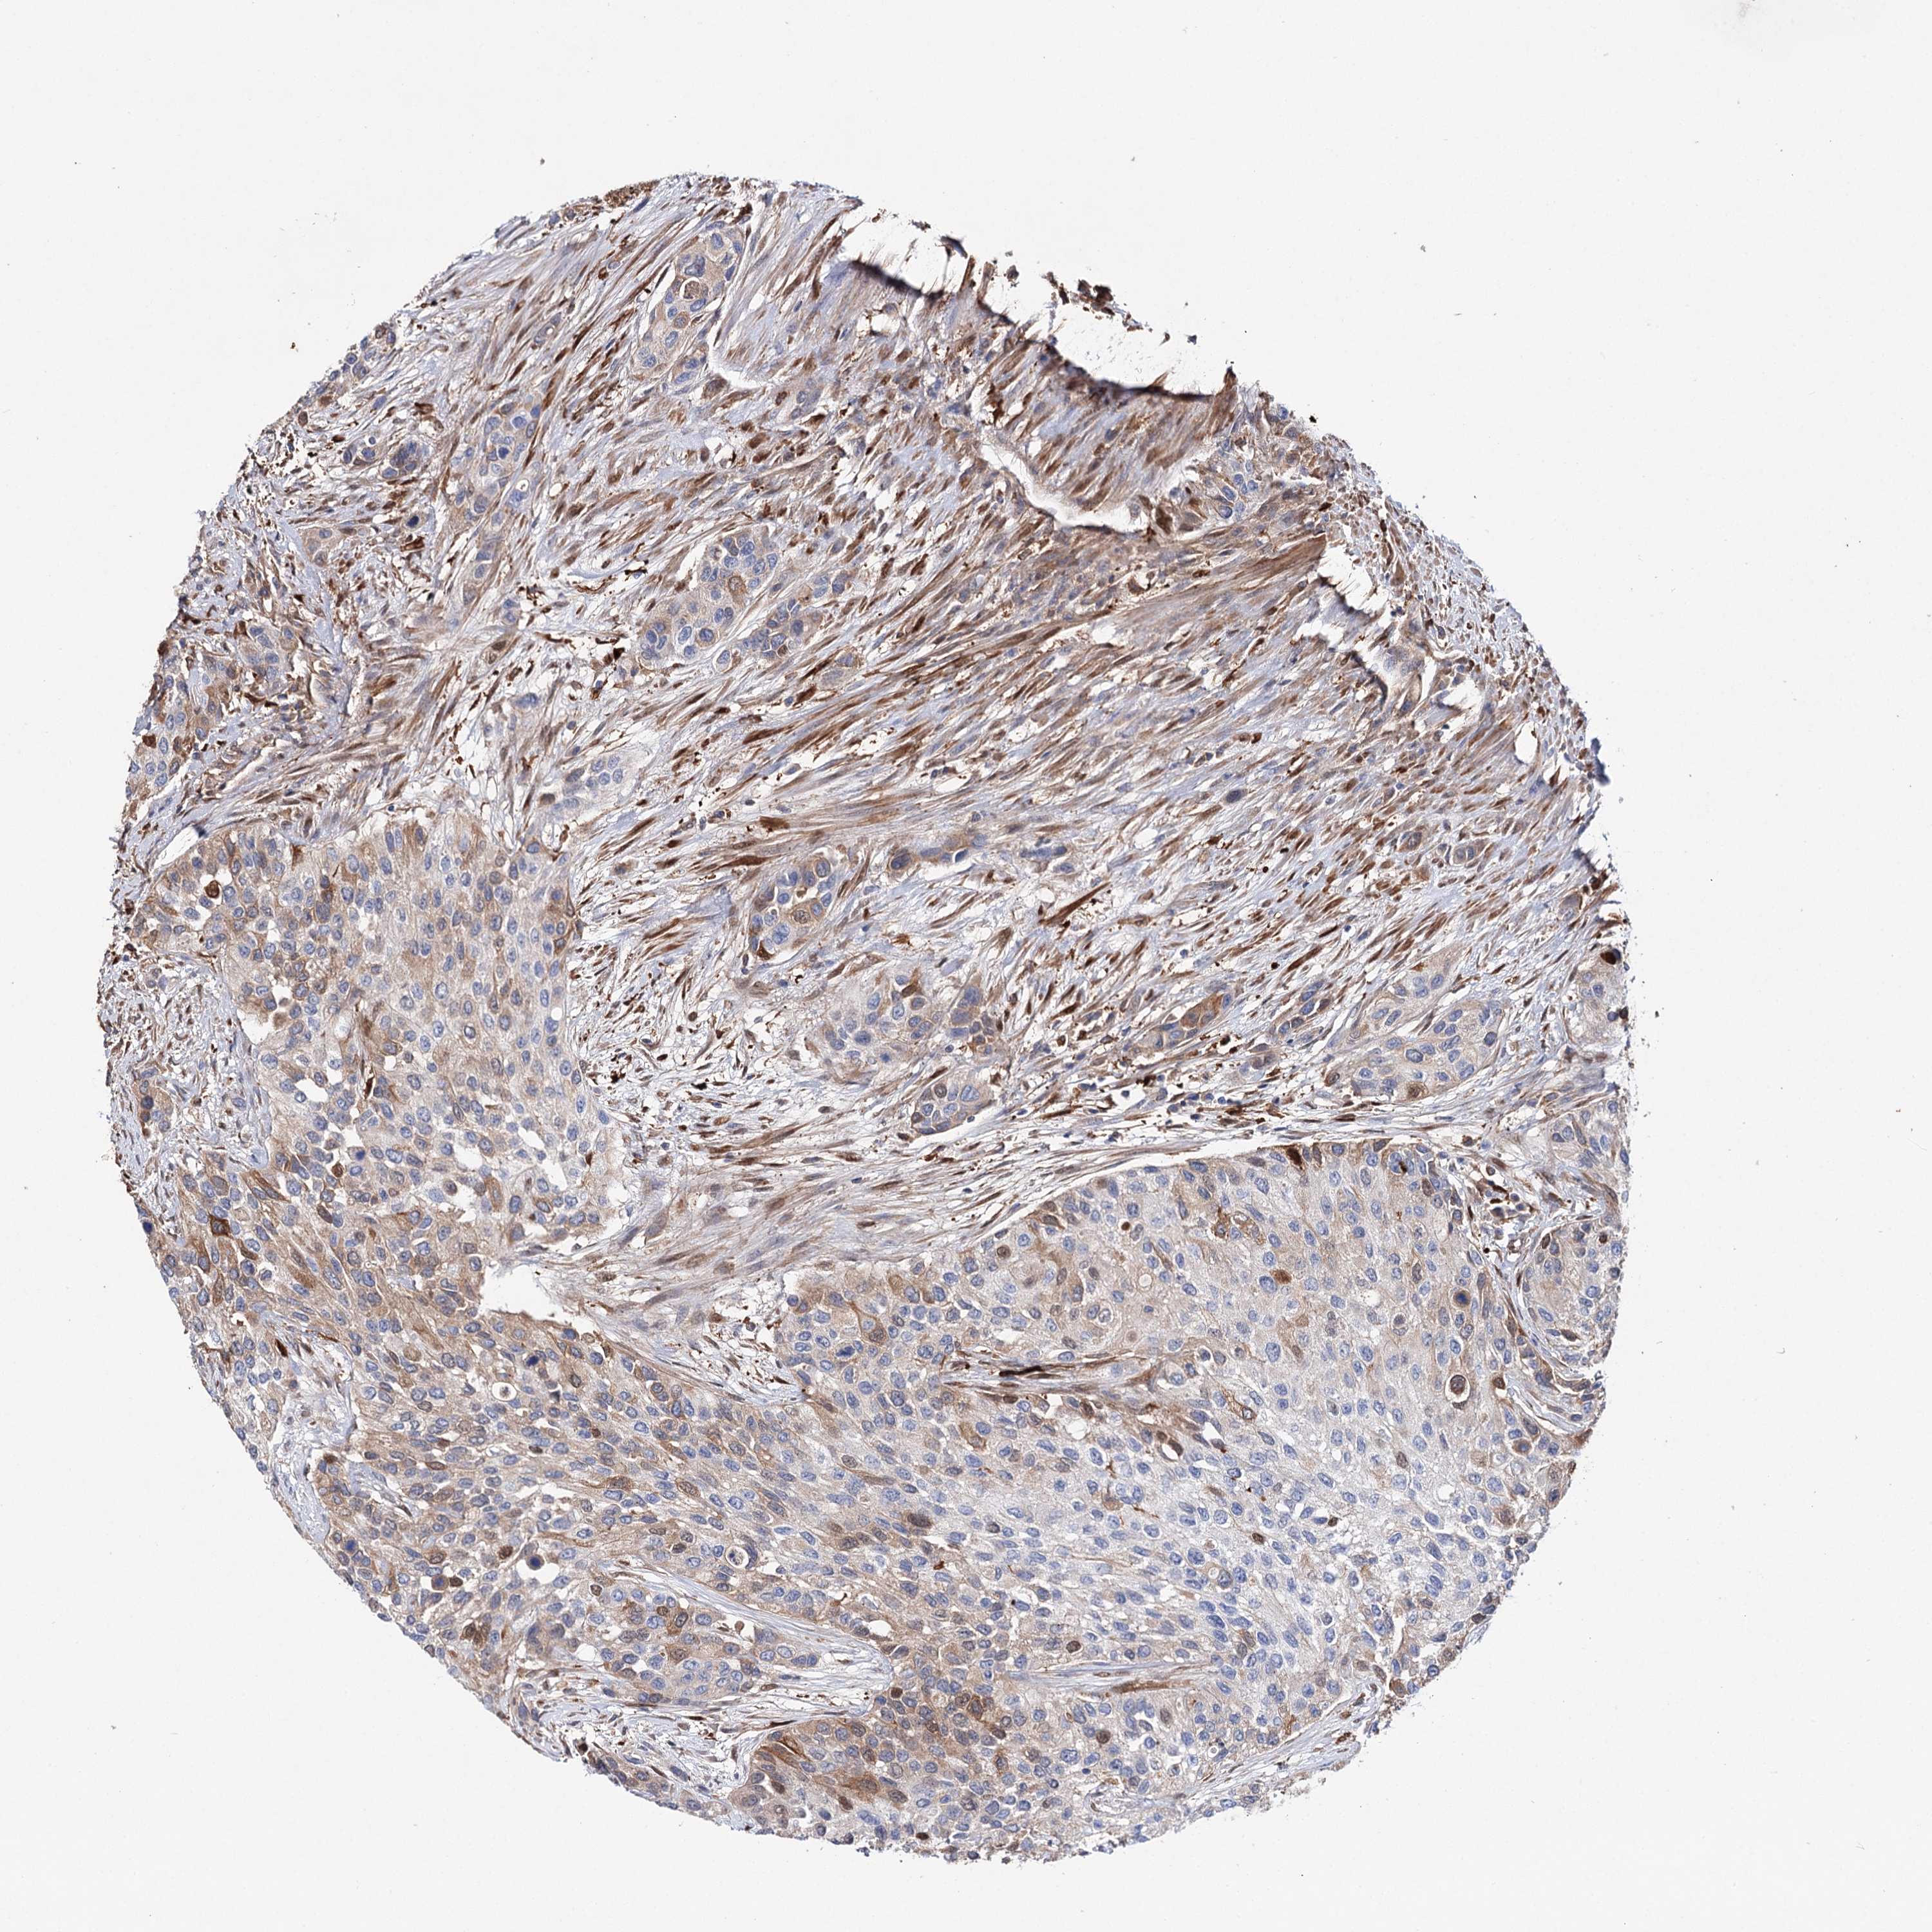

UROTHELIAL CANCER - Protein expressioni

A mouse-over function shows sample information and annotation data. Click on an image to view it in a full screen mode. Samples can be filtered based on level of antibody staining by selecting one or several of the following categories: high, medium, low and not detected. The assay and annotation is described here.

Note that samples used for immunohistochemistry by the Human Protein Atlas do not correspond to samples in the TCGA dataset.

Antibody stainingi

Antibody staining in the annotated cell types in the current human tissue is reported as not detected, low, medium, or high, based on conventional immunohistochemistry profiling in selected tissues. This score is based on the combination of the staining intensity and fraction of stained cells.

Each image is clickable and will lead to virtual microscopy that enables deeper exploration of all samples and also displays staining intensity scores, fraction scores and subcellular localization as well as patient and tissue information for each sample.

Antibody HPA037786

Antibody HPA038034

Antibody HPA038867

Antibody HPA038868

Urothelial carcinoma, High grade

Urothelial carcinoma, Low grade

Urothelial carcinoma, NOS